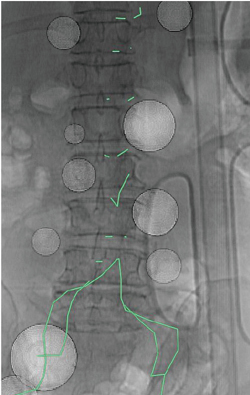

図5 転落外傷による多発出血症例

高所からの墜落により骨盤骨折や傍椎体領域に多発出血を認めた。広範な組織挫滅に伴う凝固破綻をきたしており、ヒストアクリルにより多数の血管を塞栓した。

仮想透視画像による血管分岐位置の把握は、多数の血管を選択しなければならない状況でより威力を発揮する。特に、転落外傷では複数の胸腰椎や肋骨の骨折による多発出血を伴うことがあり、腰動脈・肋間動脈を多数選択しなければならない場合がある。CT撮影から血管造影開始までの間に、10本以上の血管のパスをひとつひとつ描いている時間的猶予はないため、図5のように血管の起始部のみ点で示し、活動性出血の位置をマーキングしておく。画像診断班がそれを見ながら、術者の操作するカテーテル先端位置に対し、上下左右どの方向に動かせばいいか、目標血管は椎体のどの構造と重なっているかなどきめ細かく指示を出す。術者は透視画面だけを見てカテーテル操作に専念することができ、各血管を秒単位で選択することが可能となる。